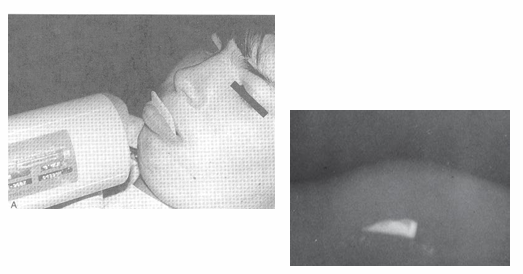

child preparation and management for radiographs

-euphemisms (camera, selfie)

-role models

-contour film- not possible with digital sensors, can damage phosphor plates

-”edge ease” (cushions that go around sensor)

-distraction

-parental help